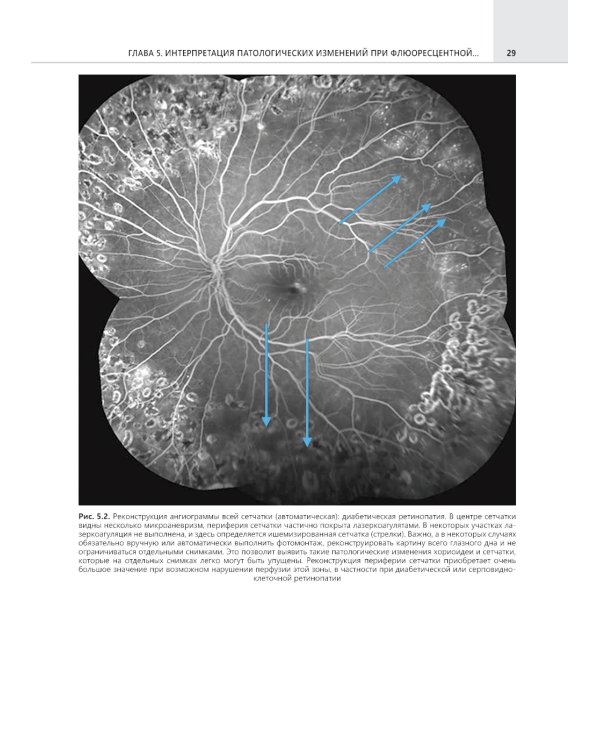

Настоящий труд является современным и исключительно актуальным изданием. Представленный материал скрупулезно проработан авторами и дополнен большим количеством иллюстративного материала, что позволяет читателю лучше понять структурные изменения при различной патологии заднего отрезка глаза, в том числе возрастной макулярной дегенерации, диабетической ретинопатии, окклюзии сосудов сетчатки и других заболеваниях. Особое внимание заслуживает интерпретация полученных результатов, что позволит специалистам документировать выявленные изменения и диагностировать патологию заднего отрезка глаза за счет большого количества приведенных примеров различной патологии заднего отдела глаза. Данное руководство предназначено не только опытным клиницистам-офтальмологам, но и студентам медицинских вузов, ординаторам и исследователям в области офтальмологии.| Издательство | ГЭОТАР-Медиа |